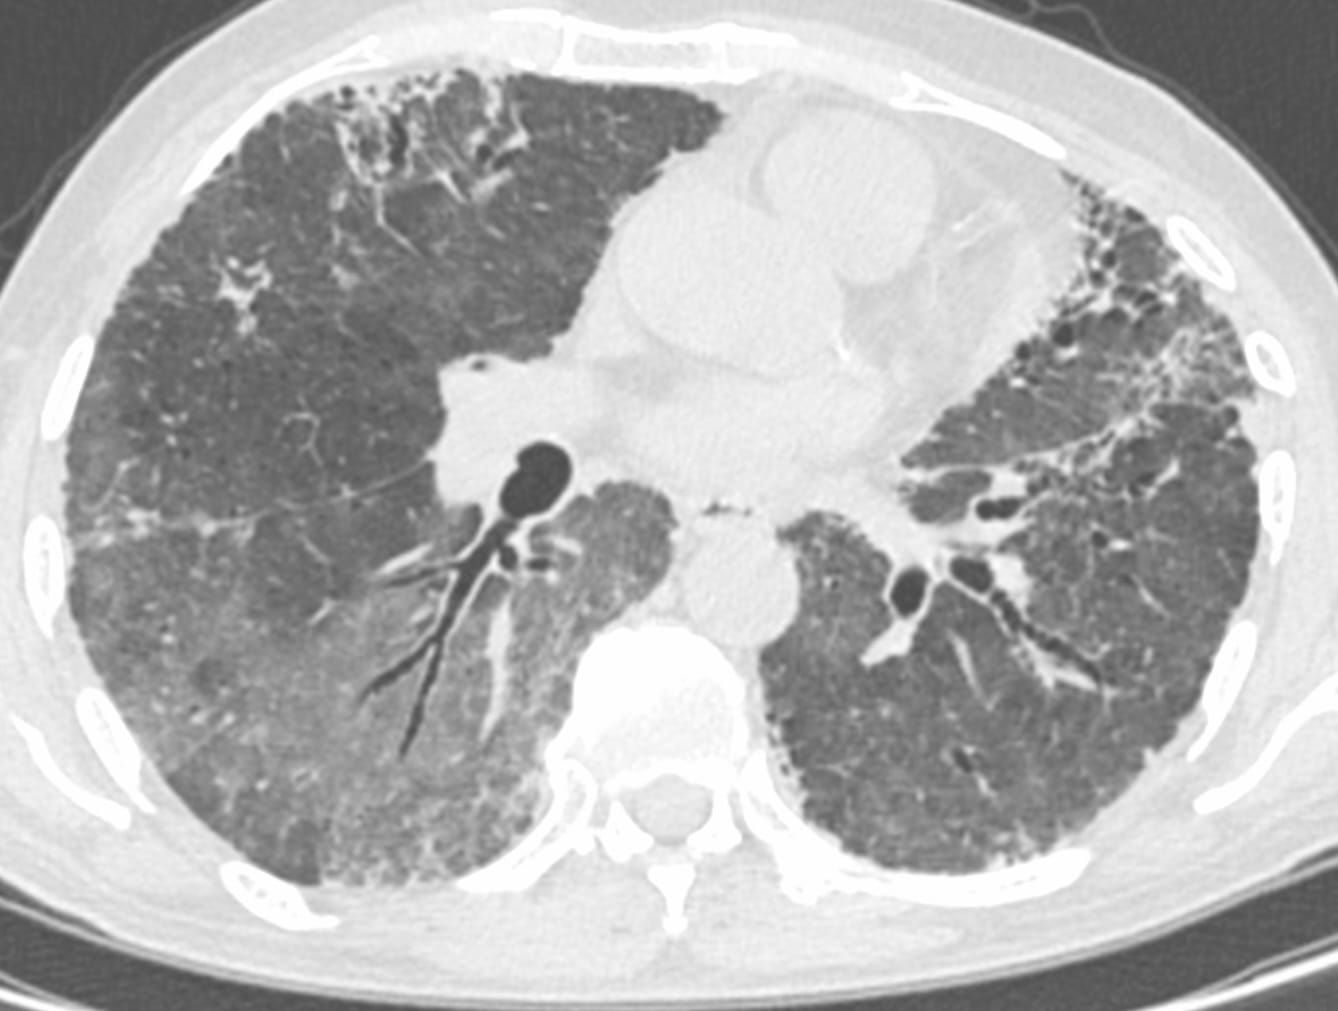

New diffuse ground glass in a pre-existing fibrosing ILD

Case 92: New Ground Glass in a Patient with a Fibrosing ILD Members Public

New ground glass in a patient with a fibrosing ILD with acute worsening is worrisome